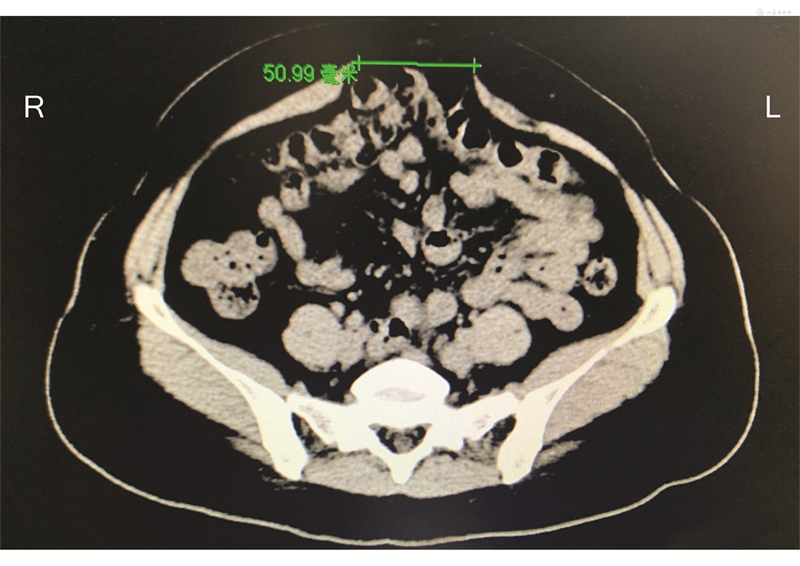

腹直肌分离较常发生于孕期、产后女性,超声检查因无创、无辐射的优点,广泛应用于临床,且其可以动态观察腹直肌分离程度,进行随访监测[13]。操作时嘱病人呈仰卧位,将超声探头长径垂直于腹白线,横向放置于腹部,在病人呼气末分别测量脐水平、脐上下2 cm位置处双侧腹直肌内侧缘距离。对于腹型肥胖病人,超声检查仍可获得较精准数据[14]。此外,CT检查(图1)和MRI检查因具有强大的图像后处理功能,可以对腹直肌分离程度、是否伴有腹腔内容物疝出等情况作出客观判断,对制订治疗方案及评价术后效果具有重要价值。临床诊断与治疗过程中,应根据病人情况、病程阶段等个体化选择恰当的测量方法。

注:绿色线为腹直肌分离宽度